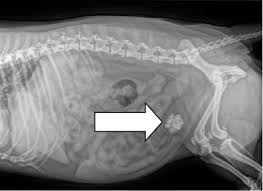

- Siêu âm hoặc X-quang: Đây là hai phương pháp chính để phát hiện sự hiện diện của sỏi thận trong cơ thể mèo.